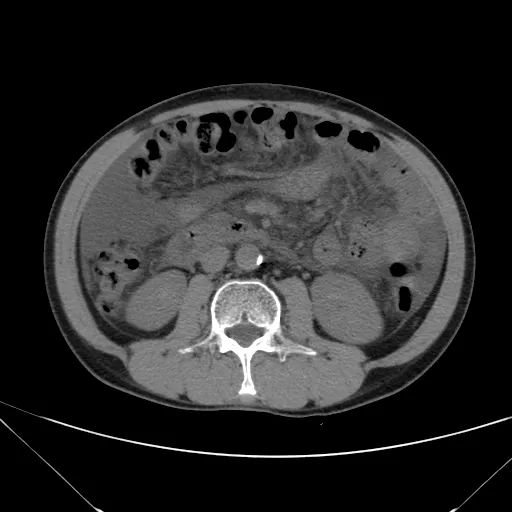

肝脏形态、密度、大小未见异常,各叶比例协调,包膜光滑,肝实质未见明确异常密度影;胆道未见扩张;胆囊形态、大小未见异常,胆囊壁光滑,其内未见异常密度影;胰腺、脾脏形态、密度、大小未见异常;双肾上腺及双肾形态、密度、大小未见异常,双输尿管未见扩张,膀胱充盈良好,壁光滑,其内未见异常密度影;前列腺/子宫及附件未见异常;胃肠道未见充盈,壁未见明确增厚;腹部及腹膜后未见肿大淋巴结。

1.肝脏、胆囊、胰腺、脾脏CT平扫未见异常。

2.双肾、输尿管、膀胱、前列腺/子宫及附件CT平扫未见异常。